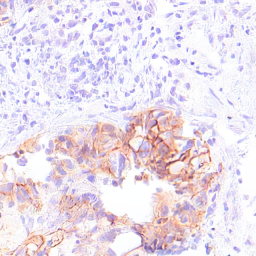

Refer to captionRefer to captionRefer to captionRefer to captionRefer to captionRefer to captionRefer to captionRefer to captionRefer to captionRefer to captionRefer to captionRefer to captionRefer to captionRefer to captionRefer to captionRefer to captionRefer to captionRefer to captionRefer to captionRefer to captionRefer to captionRefer to captionRefer to captionRefer to captionRefer to captionRefer to captionRefer to captionRefer to captionRefer to captionRefer to captionRefer to captionRefer to captionRefer to captionRefer to captionRefer to captionRefer to captionRefer to captionRefer to captionRefer to captionRefer to captionRefer to captionRefer to captionRefer to captionRefer to captionRefer to captionRefer to captionRefer to captionRefer to captionRefer to captionRefer to captionRefer to captionStyle Transfer [6]Ours (Nearby Style Cond.)Ours (Multi-Patch Style Cond.)StylesStylesStyles (selection, 3 of 10)LayoutsLayoutsLayouts

Figure 5: Image generation results with the CATCH dataset, for the style transfer baseline [6] (left), our proposed method trained with nearby patches as style source (center) and our proposed method trained with multi-patches as style source (right). Note that white represents tumor tissue in the layout images, while black includes all background structures.

Figures 4 and 5 show examples of generated images for the HER2 and CATCH dataset. The style transfer baseline [6] captures some of the staining characteristics for the HER2 dataset, but also creates some darker blurred areas, which are not commonly seen in HER2 images. On the CATCH dataset, the global color scheme is transferred to the synthetic images, but no delineation between tumor and background area is visible. For our method the generated images adhere to the spatial layout and also represent the styles in the query images for both the nearby and multi-patch configuration, even though the query images were not seen during training.